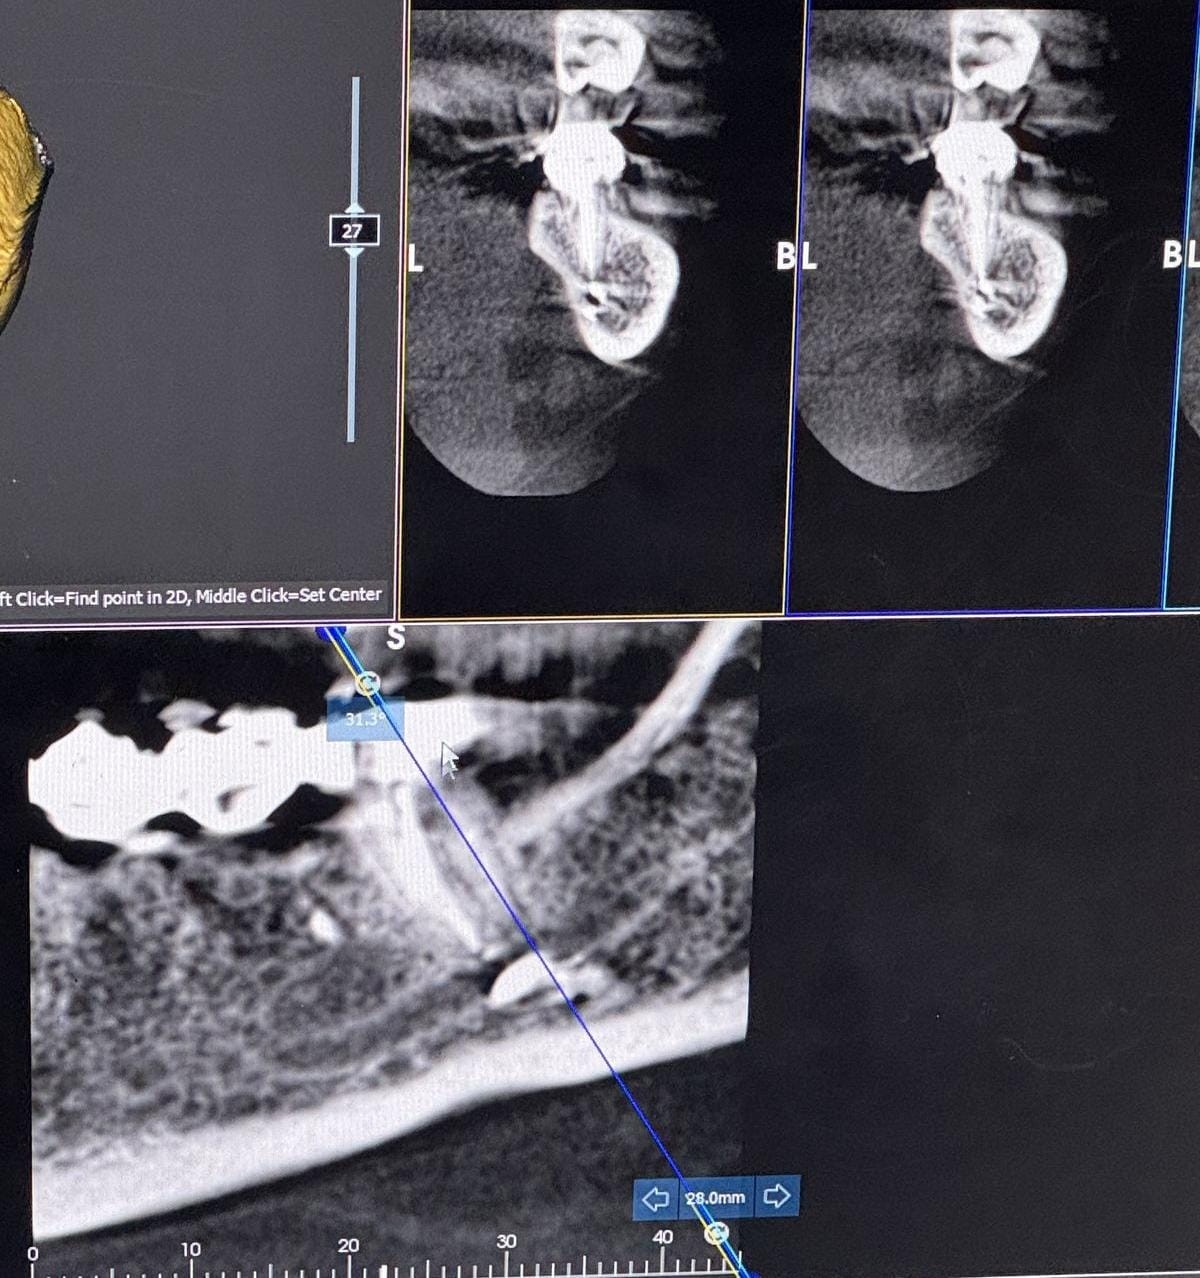

Onun sözlərinə görə, bu ilin aprel ayında diş kanalının müalicəsi zamanı adıçəkilən həkim tərəfindən istifadə olunan formaldehit tərkibli dərman maddəsi düzgün tətbiq edilməyib: “Bu səbəbdən dərman kanaldan kənara sızıb, üzümdəki sinir toxumalarına ciddi zərər verib.

Hadisədən dərhal sonra üzümdə və dodaqlarımda hissiyyatsızlıq yarandı. Buna baxmayaraq, həkim vəziyyəti ciddiyə almaraq “yod çək, keçəcək” deyib, məni evə göndərdi. Bundan sonra vəziyyətim sürətlə pisləşdi. Digər tibb müəssisəsində təcili əməliyyat edərək həmin zərərli maddəni orqanizmdən xaric etdilər. Bir gün geciksəydim, sinir toxumamda daimi iflic riski yaranacaqdı. Hazırda üzümdə hissiyyat hələ tam bərpa olunmayıb, bunun uzun müddət davam edəcəyi bildirilib”.

R.Zaxarova bununla bağlı Səhiyyə Nazirliyinə müraciət etdiyini, lakin özəl müəssisə olduğu üçün məsələyə laqeyd yanaşıldığını deyib: “Bütün bu müddət ərzində məsuliyyət daşıyan tərəf mənə heç bir köməklik göstərmədi. Həkim məni başqa bir həkimə yönləndirəcəyini dedi, lakin onu da etmədi. Əlimdə rentgen görüntüləri və əməliyyat sənədləri var”.